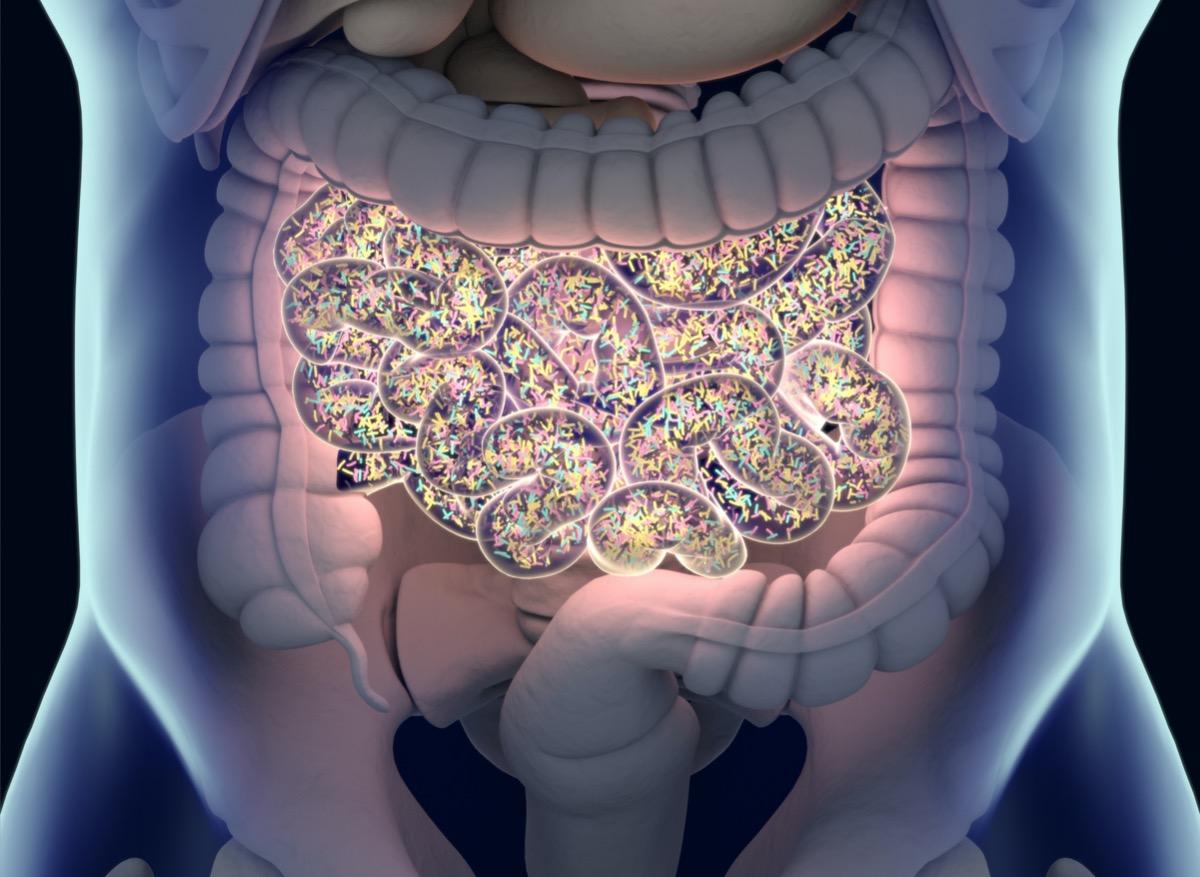

- Cette étude est l'une des rares à s'intéresser à l'impact du microbiote sur la santé humaine sur le long terme.

- Chaque personne possède un microbiote unique.

- Un déséquilibre peut être à l'origine de certaines pathologies, comme les maladies intestinales chroniques inflammatoires (MICI).

Notre flore intestinale pèse près de deux kilos : elle contient des millions de micro-organismes importants pour le fonctionnement de notre appareil digestif, pour le métabolisme et les défenses immunitaires. Toutefois, toutes les fonctions de ces bactéries ne sont pas connues. En Finlande, des chercheurs montrent qu’elles sont aussi révélatrices de notre espérance de vie. Ces spécialistes de l’université de Turku ont analysé les échantillons de selles de plus de 7 000 Finlandais adultes pour parvenir à cette conclusion. Les résultats de leur étude ont été publiés dans la revue Nature.

Les prélèvements ont été réalisés en 2002 et les analyses ont duré jusqu’en 2017, ce qui a permis aux chercheurs d’observer l’évolution de l’état de santé des participants. "Nous avons développé un algorithme capable de contrôler les données des espèces microbiennes pour trouver celles qui étaient associées à un taux significatif de mortalité", explique Leo Lahti, l’un des co-auteurs de cette étude. Avec son équipe, il a étudié toutes les branches d’ADN issues des échantillons de microbiote, puis il les a comparé aux données récoltées sur la santé des participants. Les scientifiques ont constaté que les entérobactéries sont associées à un risque plus élevé de décès, suite à des maladies respiratoires ou gastro-intestinales, lorsqu’elles sont présentes en grande quantité. "Notre mode de vie peut avoir un impact sur leur quantité", ajoute Teemu Niiranen, professeur de médecine à l’université de Turku.

Pour les chercheurs, ces résultats sont une avancée pour la prise en charge des patients. "En étudiant la composition du microbiote intestinal, nous pourrions préciser les prévisions de mortalité, même en prenant en compte d’autres facteurs de risque important comme le tabac ou l’obésité", souligne Teemu Niiranen. Ces millions de bactéries seraient aussi associées à des pathologies comme le cancer ou le diabète. Récemment des chercheurs turcs ont observé un lien entre un déséquilibre du microbiote intestinal et la maladie de Verneuil.